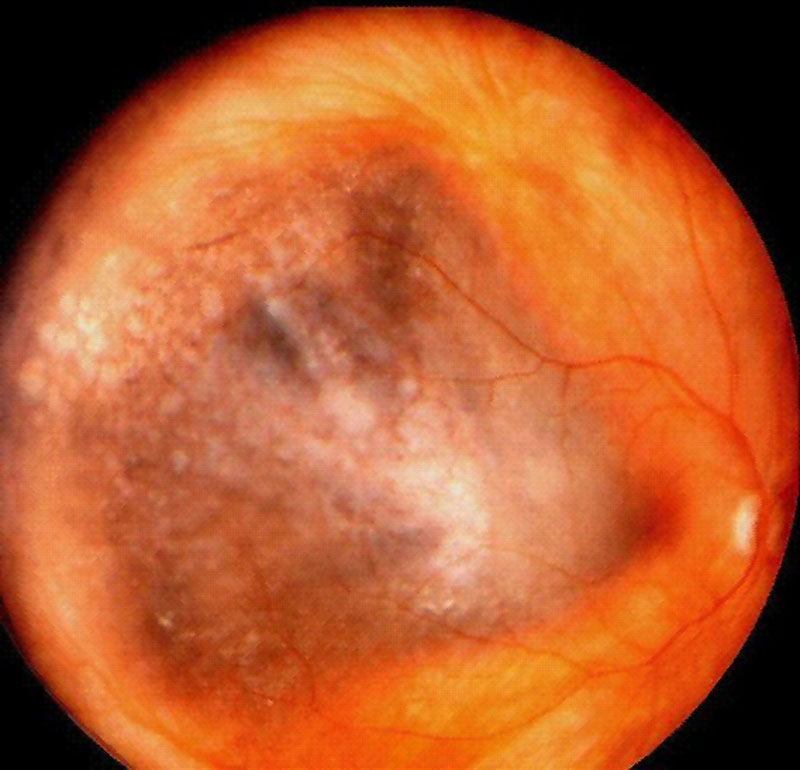

2. El nevus gigante es aquel cuyo diámetro es mayor de 10 mm, por lo que pueden simular un melanoma (Figura 10). En el 81% de los nevus gigantes exiten drusas, además de atrofia del EPR, hiperplasia del EPR. Es importante conocer que en estos casos los signos de malignización son la rapidez en el crecimiento, nodularidad en el tumor, existencia de desprendimientos serosos del EPR, pigmento naranja y una masa en forma de champiñón asociado con ruptura en la membrana de Bruch25.

Figura 10. Nevus gigante. Cortesía del Wills Eye Hospital